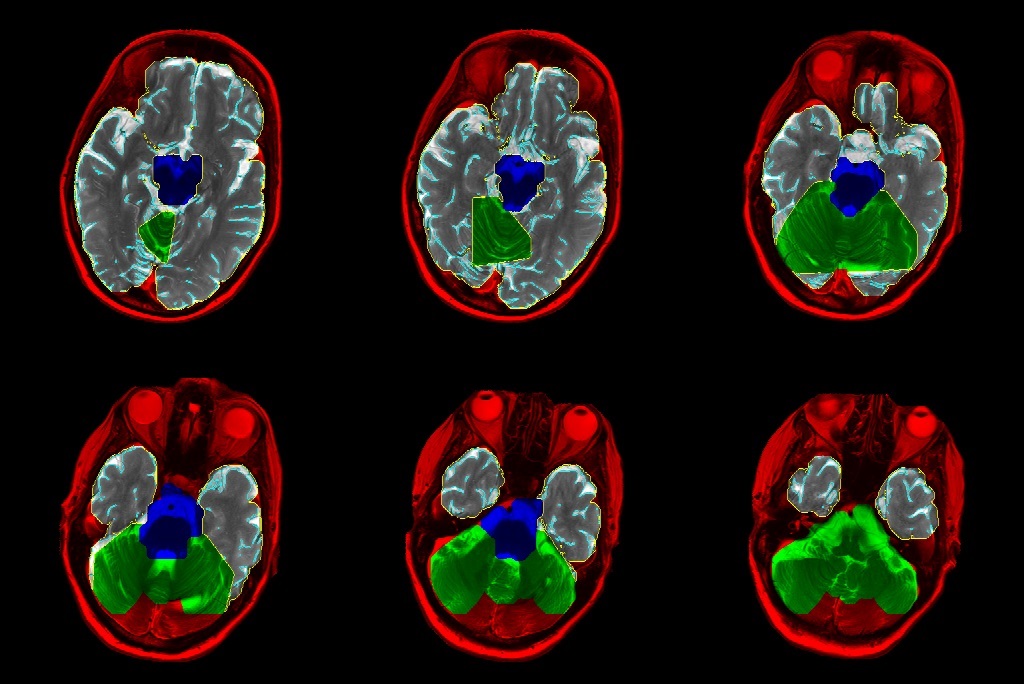

Der Mensch verliert aufgrund natürlicher Alterung, aber auch durch Krankheiten laufend Nervenzellen im Gehirn. Die Thalamo-Corticale Reserve (TCR) beschreibt das Volumenverhältnis von Nervengewebe zu Gehirnwasser und ist ein Mass für die Hirnatrophie (Gehirnschwund). Bei der Behandlung von neurologischen Erkrankungen (z. B. Parkinson) mit fokussiertem Ultraschall haben die Neurologen von SoniModul die Erfahrung gemacht, dass bei zu weit fortgeschrittener Hirnatrophie keine Verbesserung des Gesundheitszustandes eintritt. Bisher wurde die TCR im Vorfeld der Behandlung anhand von MRT-Bildern qualitativ abgeschätzt. Mithilfe des entwickelten Softwaretools kann die TCR nun automatisiert und quantitativ bestimmt werden. Die Software segmentiert anhand der Bilddaten mittels diverser Bildbearbeitungsverfahren und eines Machine-Learning-Modells das Grosshirn. Die Pixel des Hirngewebes und der Hirnflüssigkeit werden gezählt und der daraus resultierende quantitative TCR-Wert wird ausgegeben.